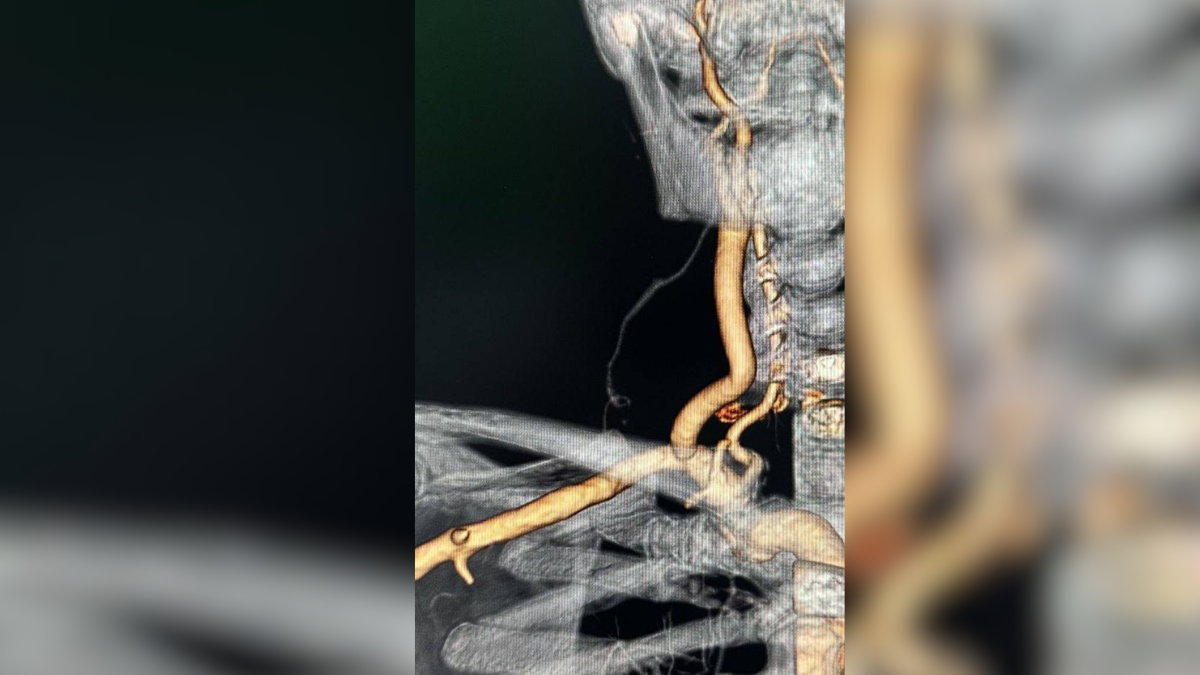

«У більшості пацієнтів звуження зазнає початковий відділ внутрішньої сонної артерії. При такому ураженні варіанти операцій давно відпрацьовані. Однак до нас звернувся пацієнт з дуже рідкісним ураженням – з цілковитою непрохідністю загальної сонної артерії та звуженням більше 60 % початкового сегменту внутрішньої сонної артерії. Кров у цю артерію потрапляла лише зворотньо з зовнішньої сонної артерії через мікроскопічне сполучення між ними шириною 1,4 мм. Щоб не допустити повного припинення кровотоку по внутрішній сонній артерії з імовірним розвитком тяжкого інсульту, була проведена операція, при якій кров спрямували до головного мозку та обличчя через штучний шунт від підключичної артерії («підключично-внутрішньосонне шунтування з реімплантацією зовнішньої сонної артерії в протез»)», – розповідає професор, судинний хірург Ростислав Сабадош.